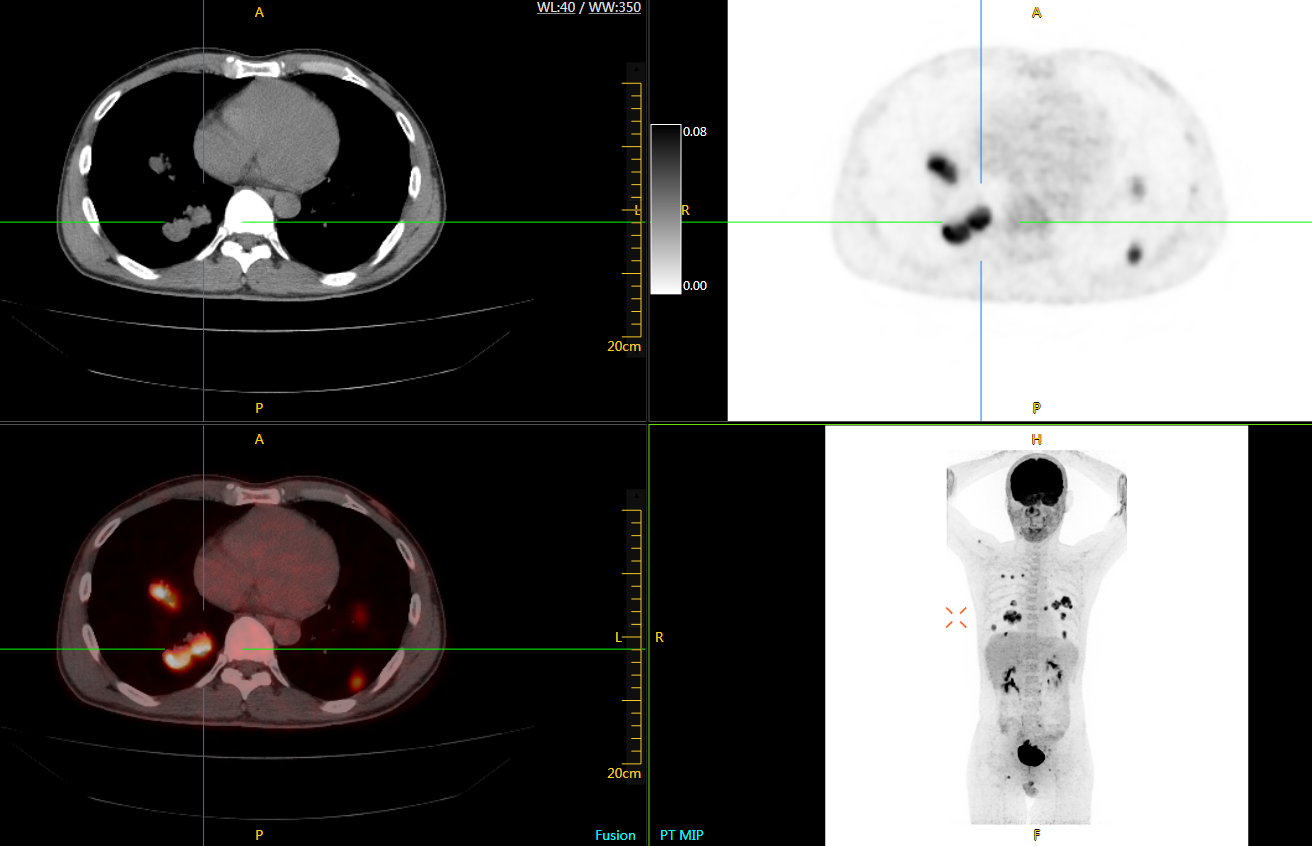

直腸癌

男,45歲,直腸癌術(shù)后9個(gè)月,發(fā)現(xiàn)肺占位

臨床診斷:直腸區(qū)術(shù)后改變,復(fù)發(fā)伴骶骨受累,雙肺多發(fā)轉(zhuǎn)移